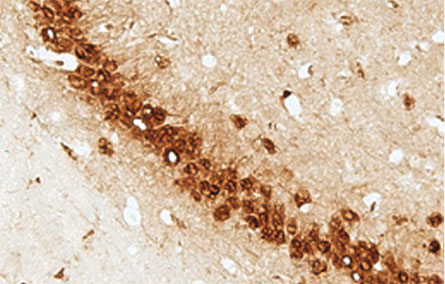

These slow-to-grow brain networks are the first to go in old age, neuroscientist Gwenaëlle Douaud of the University of Oxford and colleagues found. Networks of nerve cells (the gray matter) are guided by a “last in, first out” rule, brain scans of 484 people from 8 to 85 years of age indicate. “What we show is a precise mirroring for these regions,” she says.

These networks, which reach their peak around age 39 for men and age 41 for women, handle sophisticated jobs, like merging multiple kinds of information together, she says. And sure enough, people with seemingly healthier neural connections had better memories, Douaud’s team reported in the Proceedings of the National Academy of Sciences in 2014.

Source: G. Douaud et al/PNAS 2014